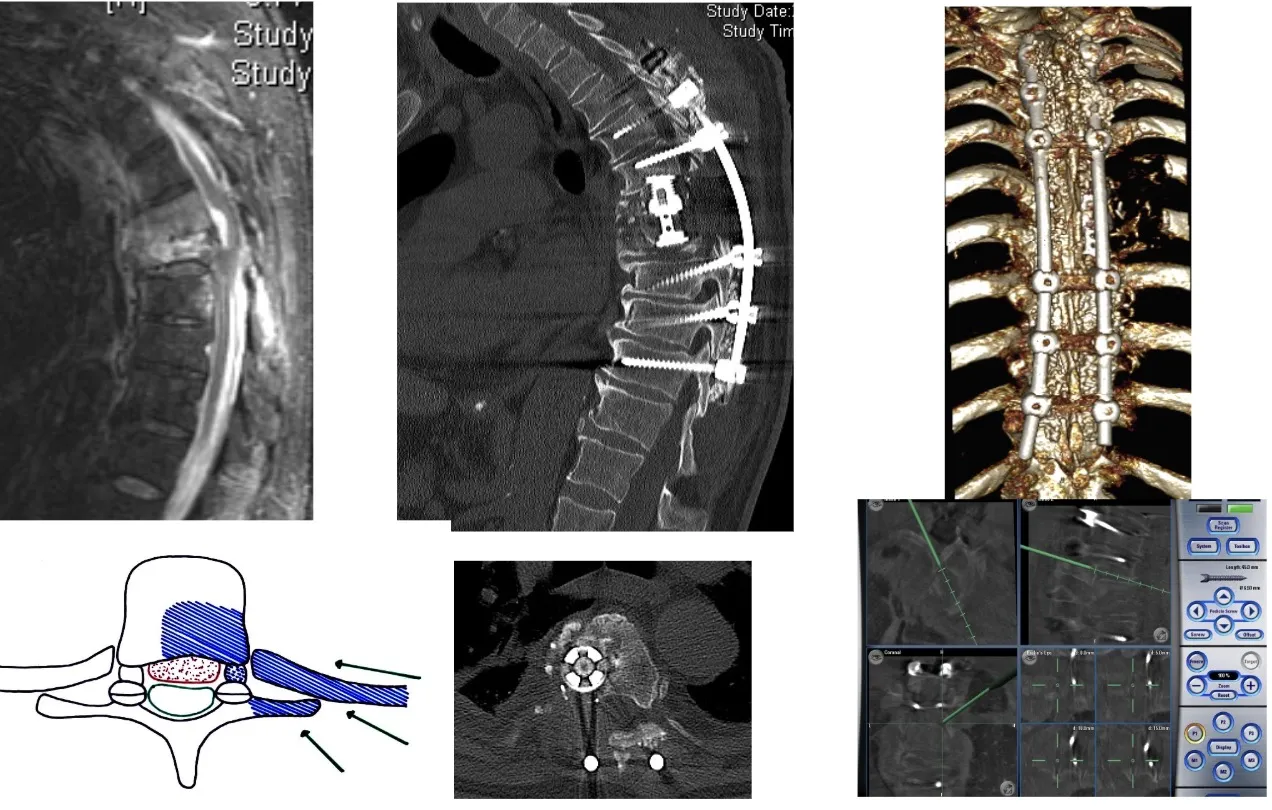

También es posible realizar el abordaje por vía posterior, a través del cual se pueden efectuar tanto la resección de los tumores como la colocación de los sistemas de fijación necesarios para estabilizar la columna, tal como se observa en la figura. Este abordaje permite al cirujano acceder directamente a las estructuras posteriores vertebrales y realizar una descompresión neurológica precisa cuando existe afectación del canal raquídeo.

En el caso de la transición entre la columna torácica y la lumbar, la cirugía resulta especialmente compleja debido a la presencia del diafragma y a las particularidades anatómicas de esta región. En estas situaciones pueden ser necesarios abordajes combinados o específicos, que permitan acceder tanto por vía anterior como posterior. A menudo es preciso reconstruir el soporte anterior de la columna mediante injertos o prótesis para restaurar la estabilidad y garantizar que la columna se mantenga firme y alineada tras la intervención.

Hoy en día disponemos de la capacidad técnica y humana, gracias a la colaboración con otros especialistas, para llevar a cabo grandes intervenciones quirúrgicas en la columna lumbar, procedimientos que hace apenas unos años presentaban una morbilidad tan elevada que los hacía desaconsejables tanto para los cirujanos como para los propios pacientes.

Otro de los grandes avances tecnológicos, ya bastante conocido por muchos, es el neuronavegador. En el caso de la cirugía de columna, este sistema utiliza un TAC intraoperatorio obtenido mediante un equipo radiológico motorizado que rodea al paciente durante la intervención. A partir de esas imágenes, el cirujano dispone de una representación tridimensional precisa de la anatomía en tiempo real y puede orientarse con un margen de error inferior a un milímetro. De este modo, tanto en cirugía abierta como bajo microscopio, es posible conocer con exactitud la posición de los instrumentos y visualizar la estructura ósea y nerviosa del paciente en cada momento. Además, el sistema permite realizar controles intraoperatorios inmediatos, verificando el resultado antes de que el paciente abandone el quirófano.